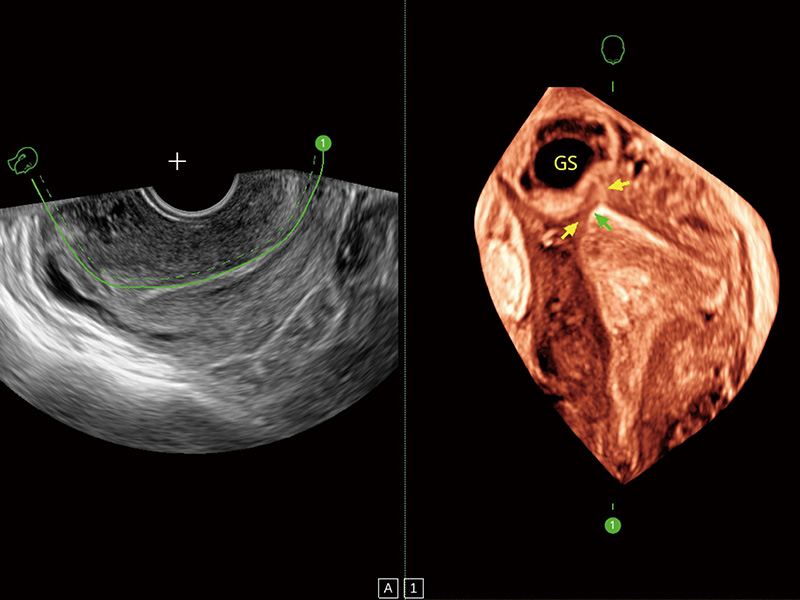

超声引导下胚胎移植

宫外孕血流